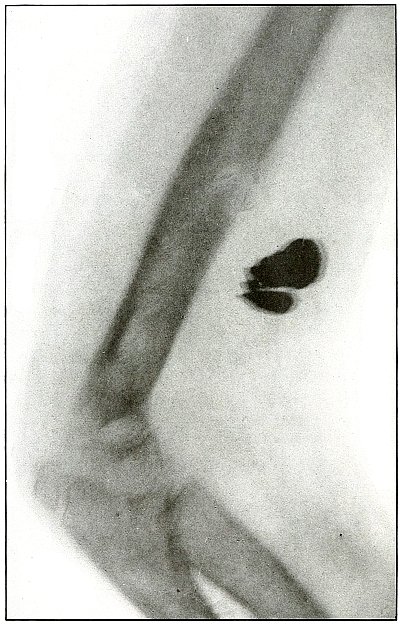

Plate 57.

[Pg 125]

Rifle—Plate 57.

LOWER EXTREMITY.

Gunshot Fracture About the Middle of the Femur,

with Lodgment of the Fragments of a Deformed Bullet.

The course of the missile was transverse. All of the remaining energy

of the retarded velocity of the short range of a ricochet shot was

stopped by the bone with the result of a long splitting fracture, and

the lodgment of one large and a few small fragments of the missile.

The small notched metal fragment lying to the right of the upper

bone fragment is a small bent piece of the jacket, detached from the

greatly deformed lead core, which can be faintly seen lying behind the

lower end of the left side of the upper bone fragment.

The treatment is extension with lateral compression, although this